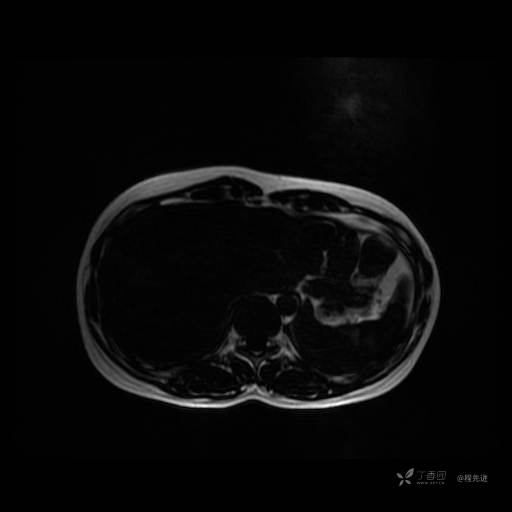

MR平扫+增强

每个序列一张图像(图像太多了,恕不一一发上来)